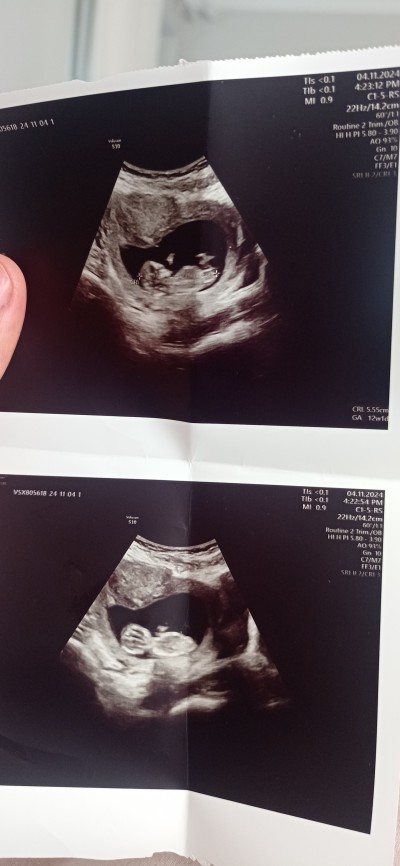

Kızlar ultrason fotografiyla bilenler oluyor ben anlamıyorum tahminde bulunabilirmisiniz

Gebelik haftası 12

Erkeğe benziyo tahminde bulunmadı mi doktor

Çıkıntısı yok dedi bacak arasında  kıza benziyor dedi ama 10 gün sonra anlarım dedi merak ettigimden burdanda sormak istedim

Erkeğe benziyor öğrenince yaz canım ne zmn kontrol

Bende çıkıntı göremedim kıza  benzettim cikinti yok gbi duruyor öğrenince yazın ben de merak ettim.